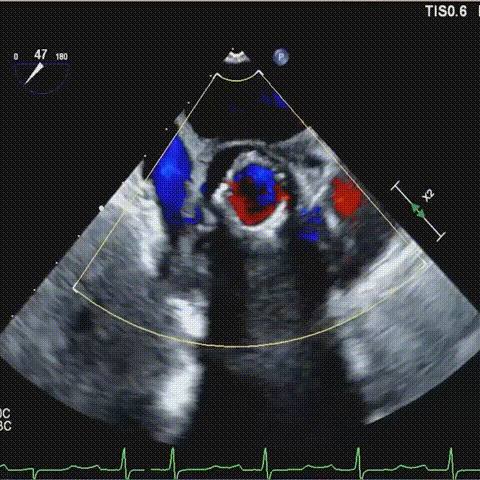

术后食道超声-短轴color

术后食道超声-长轴-color

术后食道超声-长轴color